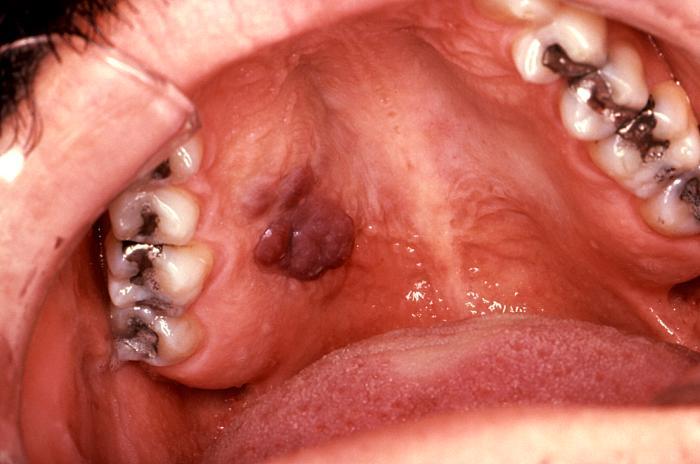

- HIV-associated Kaposi sarcoma (KS): typically characterized by violaceous vascular lesions on skin [Fig 1], mucous membranes [Fig 2] and/or viscera (e.g., GI tract and lungs).

KS mucosal lesion

Intraoral KS in patient with AIDS. About 10% of patients with advanced AIDS will have mucosal lesions of KS. Lesions may be small to larger, nodular growths.

Source: CDC, S. Silverman DDS San Francisco